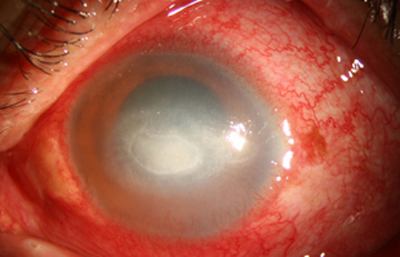

En su evolución se observará aumento del edema, agrandamiento y coalescencia de los infiltrados formando un anillo, (Figura 9, 10 y 11) que progresa hacia la formación de un absceso (Figura 12, 13 y 14), queratolisis superficial, adelgazamiento y perforación corneal (Figura 15 y 16).

Fig. 12 Síntomas de 15 días evolución

Fig. 13 Síntomas de 15 días evolución

Fig. 14 Síntomas de 15 días evolución